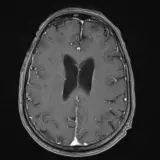

Over 2,100 interactive radiology cases, curated by radiologists for your level of training. Scroll, window, and view cases full screen — just like on PACS. Click linked findings in each writeup to jump straight to them on the image. Cases include sample reports, a focused discussion section, original illustrations, and videos.

Neuro Fellowship — a course tailored for fellows and practicing radiologists with in-depth reviews of advanced neuro topics like brain tumors, featuring rare diagnoses, differentials, and clinical pearls.

完全交互式病例,配备您在 PACS 上期待的各项工具——滚动、调窗、缩放、平移、测量、ROI 和全屏模式。

丰富的标注直接在病例图像上突出关键发现。点击病例讲解中的关联发现,即可跳转至其在扫描上的精确位置。

像在工作站 PAC 上一样滚动、平移、调窗和缩放